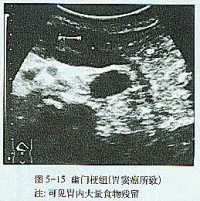

大多起病缓慢,迷走神经切断术者常于术后第2周开始进流质饮食后发病。主要症状有腹胀、上腹或脐周隐痛,恶心和持续性呕吐。呕吐物为混浊的棕绿色或咖啡色液体,呕吐后症状并不减轻。随着病情的加重,全身情况进行性恶化,严重者可出现脱水、碱中毒,并表现为烦躁不安呼吸急促、手足抽搐血压下降和休克。突出的体征为上腹膨胀,可见毫无蠕动的胃轮廓,局部有压痛叩诊过度回响,有振水声。脐右偏上出现局限性包块,外观隆起,触之光滑而有弹性、轻压痛,其右下边界较清,此为极度扩张的胃窦,称“巨胃窦症”,乃是急性胃扩张特有的重要体征,可作为临床诊断的有力佐证。

实验室检查可发现血液浓缩、低血钾、低血氯和碱中毒。立位腹部X线片可见左上腹巨大液平面和充满腹腔的特大胃影及左膈肌抬高。

实验室检查可发现血液浓缩、低血钾、低血氯和碱中毒。立位腹部X线片可见左上腹巨大液平面和充满腹腔的特大胃影及左膈肌抬高.